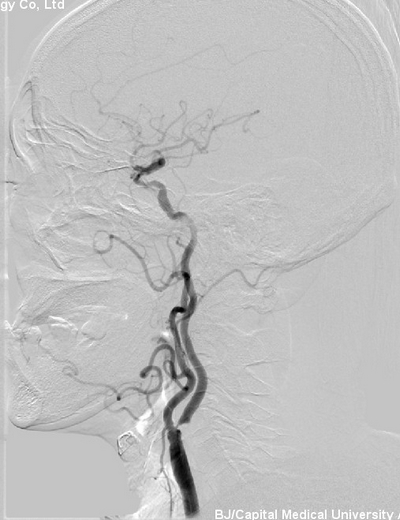

入院后患者行DSA检查:左颈内动脉重度狭窄。